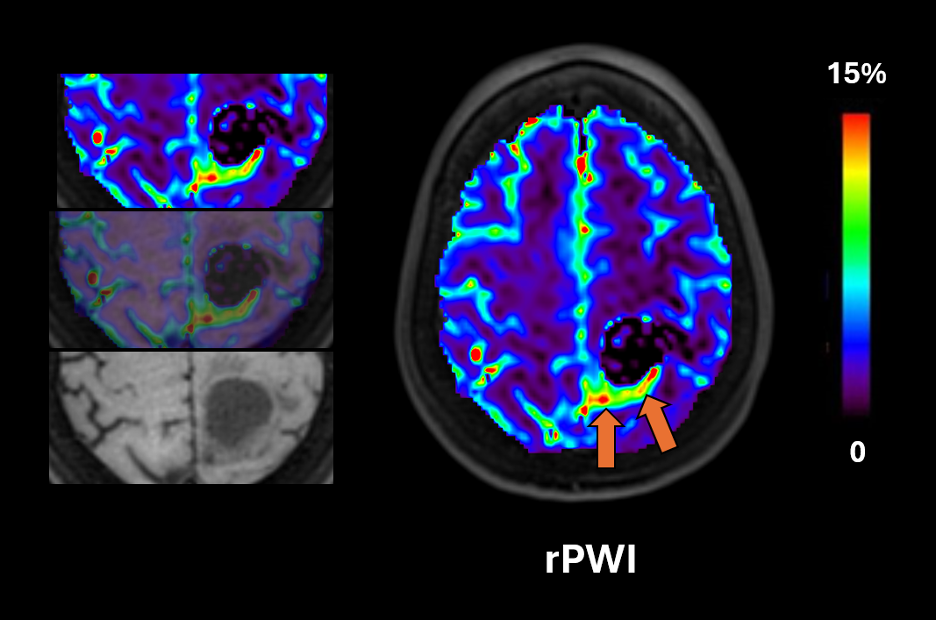

Durch die Kombination modernster magnetischer Markierung des Blutflusses mit präziser mathematischer Modellierung erzeugt pCASL hochauflösende Perfusionskarten und liefert quantitative Messungen des zerebralen Blutflusses. Solche genauen Daten sind entscheidend bei der Diagnose und Behandlung neurologischer Erkrankungen wie Schlaganfällen, Demenz oder Hirntumoren.

Ob Ischämie bei Schlaganfall, Perfusionsveränderungen bei Alzheimer oder Überwachung von Hirntumoren